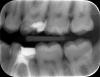

Наконец решил заняться зубами, т.к. стоматологов побаиваюсь, обращался редко. Сейчас мне 28 лет, три мертрых 6-ки, нервы были удалены более 6-8 лет назад. Хочу не спеша и спокойно привести зубы в хорошее состояние, чтобы они мне прослужили максимально долго, чтобы я все-таки не потерял их и в старости не думал про имплантацию. Конкретно сейчас интересует нижняя левая шестерка, вот она:

Изначально поводом послужило то, что пломба отходит спереди, и туда попадает пища, и в зубе, под пломбой, скорей всего, уже образовался серьезный очаг кариеса. Думал поставить пломбу, но специалсты говорят, что уже надо коронку. Какие вы посоветуете варианты? Эстетически мне все-равно, как он будет выглядеть. Главное, подчеркиваю - надежность, долговечность.

Перелечить-и вкладки, коронки. Седьмые нижние тоже требуют внимания: кариес. На 26 пломбу нужно менять. На 27, скорее всего, кариес на передней контактной пов-ти.